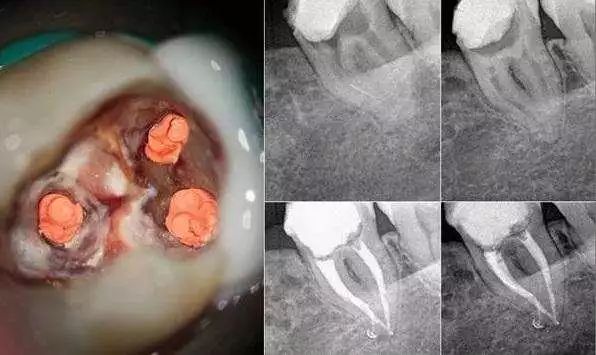

通过一组病例来了解下:

- 术前X光片:红圈处清晰显示牙体龋坏,已影响牙髓,需做根管治疗

- 术后X光片:显微镜下热牙胶根管治疗后,可见充填严密到位